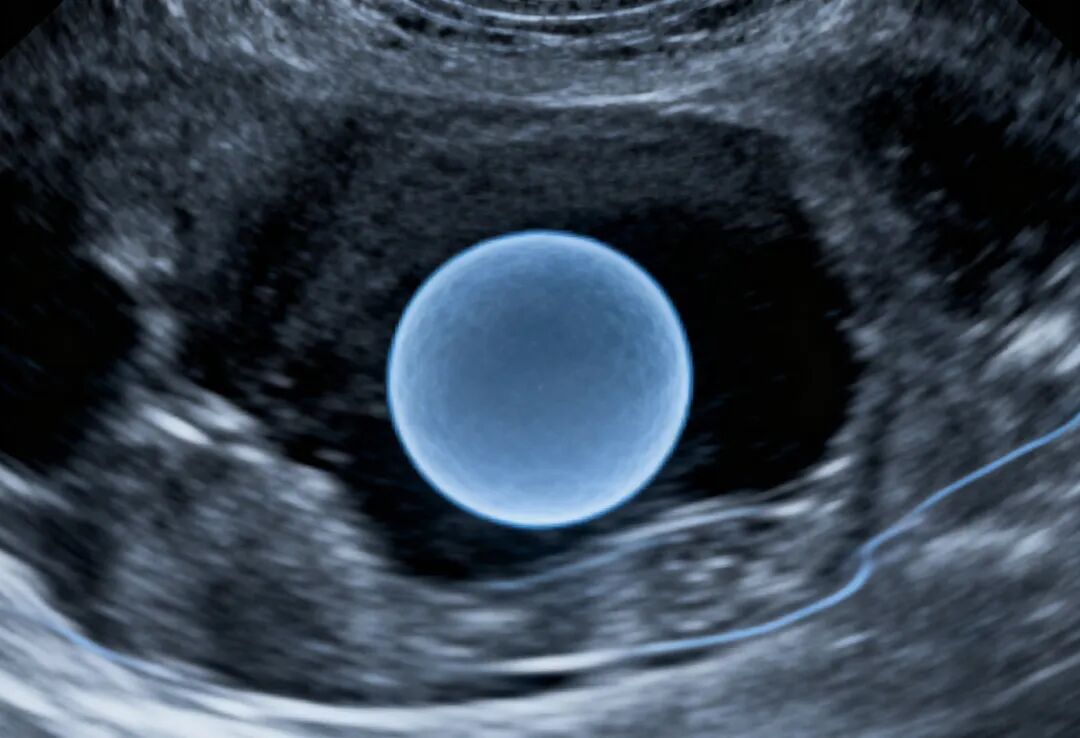

简单来说,女性做试管婴儿的“黄金年龄”是25岁到35岁之间,尤其是30岁之前是最佳时机。

这背后的核心原因是女性的卵巢功能和卵子质量会随着年龄增长而显著下降。我们可以将年龄分为几个阶段来理解:

· 全面身体检查:夫妻双方在进入周期前,应进行全面的生育力评估。女性包括性激素六项、AMH(抗穆勒氏管激素)、阴道B超(查基础卵泡数)等;男性包括精液常规分析、精子形态学、DNA碎片率等。这有助于医生制定最合适的方案。